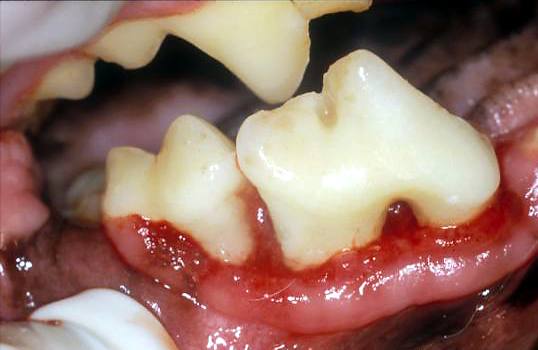

Gingival Recession

It is possible for the inflamed gingiva to recede apically. Once the microbes of periodontal disease come within 0.5mm of the bone crest it also recedes and all the tissues move apically in their normal relationship without forming a pocket.

The net result is exposure of the cemento-enamel junction and root surface but typically, no increase in sulcar depth and no pocket.